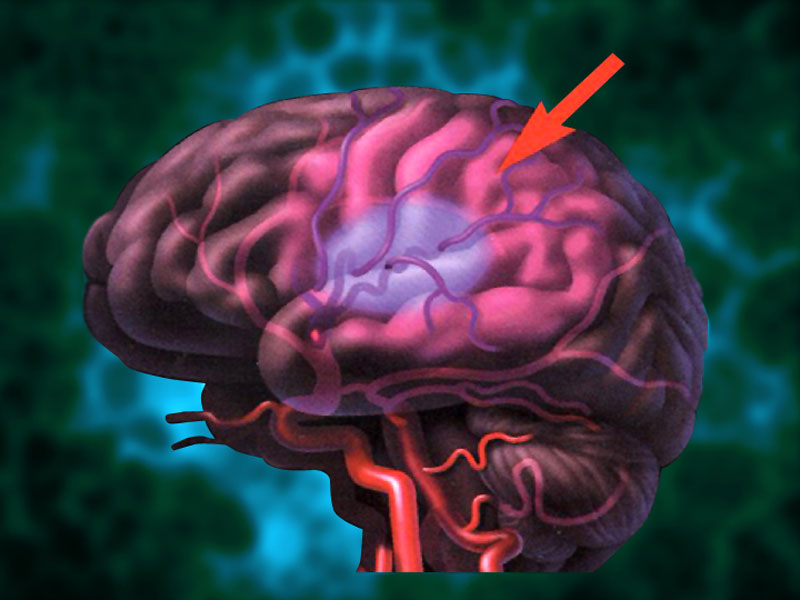

Ишемический инсульт левой стороны: симптомы и реабилитация